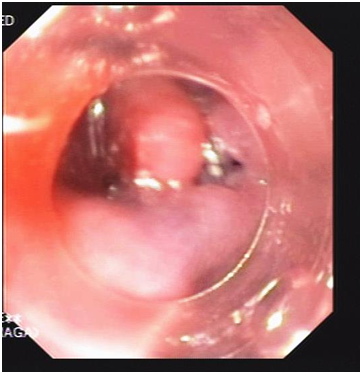

Another upper endoscopy was done and a distal tear was visualized at the distal end (Figure 2), Over-the-scope clip (OTSC) was used to close this tear (Figure 3) (Video). After the closure of the oesophageal, tear with OTSC, CT gastrografin was performed which showed minimal oesophageal leakage (Figure 4).

Figure 2 Upper endoscopic picture showing the oesophageal tear visualized at the distal end.

Figure 3 Upper endoscopic picture showing the use Over-the-scope clip (OTSC) to close oesophageal tear.